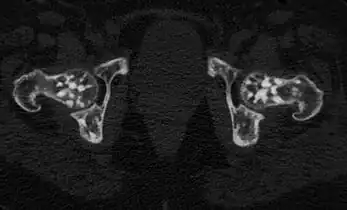

Osteopoikilosis of the hips on CT.

In terms of the diagnosis Osteopoikilosis is radiographically evaluated via the presence of multiple symmetrical circular sclerotic opacities [2]

The radiographic appearance of osteopoikilosis on an X-ray is characterized by a pattern of numerous white densities of similar size spread throughout all the bones. This is a systemic condition. It must be differentiated from blastic metastasis, which can also present radiographically as white densities interspersed throughout bone. Blastic metastasis tends to present with larger and more irregular densities in less of a uniform pattern. Another differentiating factor is age, with blastic metastasis mostly affecting older people, and osteopoikilosis being found in people 20 years of age and younger.